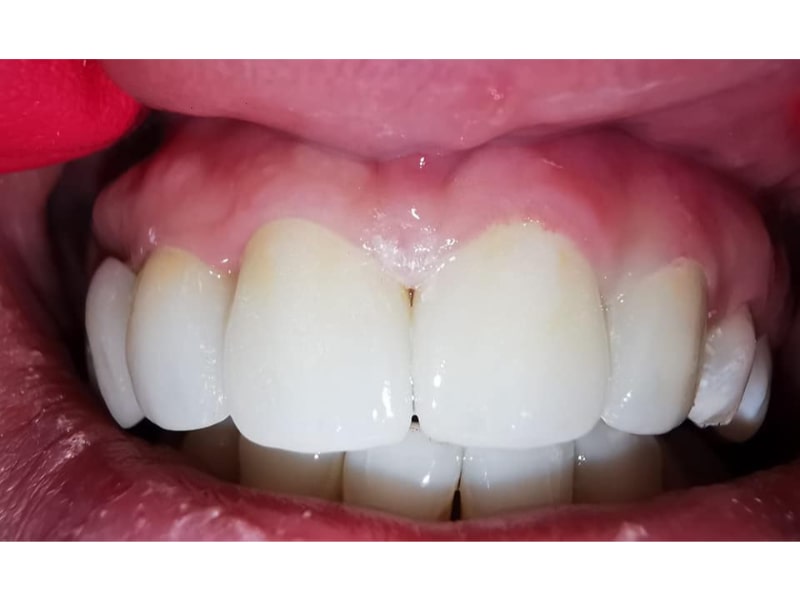

Zirconiu Multilayer